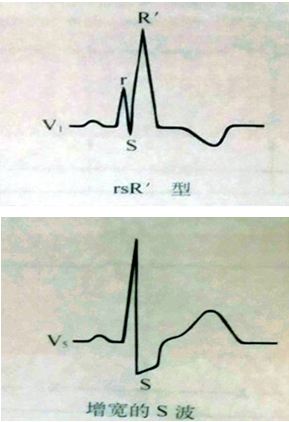

4、M波

M波是指QRS波群程序“M”形态,主要见于右束支传导阻滞,V1和V2导联上出现“M”形表示右束支传导阻滞,这里的“M”形是指出现两个R波,QRS波群呈现rsR’、RSR’或rR’形态。而与V1、V2导联对应的V5、V6导联则会出现与之相对的类似导致的宽S波,具体见下图。

而判断束支传导阻滞是否完全,主要看QRS波群的时限,QRS波群>0.12s,就是完全性的,反之就是非完全性的。具体如下图。

图11